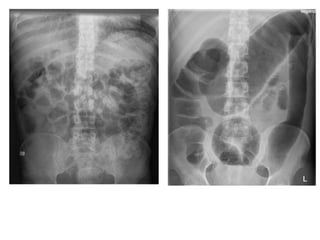

• If the patient has a history concerning for intestinal

obstruction

• Abdominal flat and erect films (or left lateral

decubitus films if pt cannot stand)

• In cases of complete or partial intestinal

obstruction, these films may demonstrate air-fluid

levels or dilated bowel

• Clinical suspicion for intestinal obstruction despite a

normal chest and abdominal series of radiographs, then

abdominal CT with PO and IV contrast may be

necessary